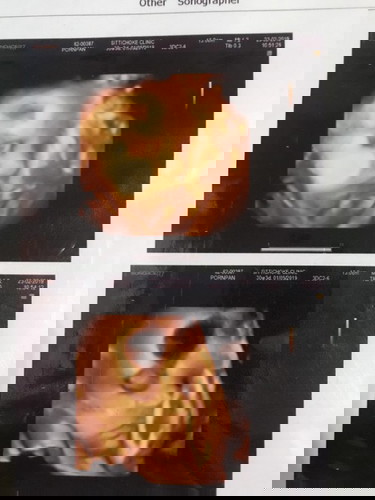

ซาวด์4มิติ

ของแม่ซาวด์ตอนน้องตื่นไงค่ะ ? บ้านนี้ซาวด์ตอนน้องหลับ 😅

น่าจะปรกตินะคะเพราะน้อง7เดือนก็ลืมตาได้แล้วค่ะแต่ไม่ค่อยให้เห็นตอนซาว